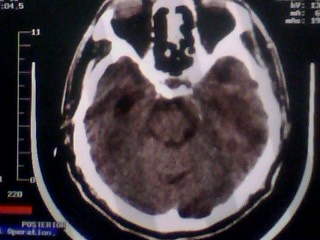

以下是引用随光逐影在2010-1-7 14:49:00的发言:[br]1)结合病史,考虑多发性脑转移瘤可能性大;建议行ct增强扫描检查。2)大脑镰下疝。3)脑积水。